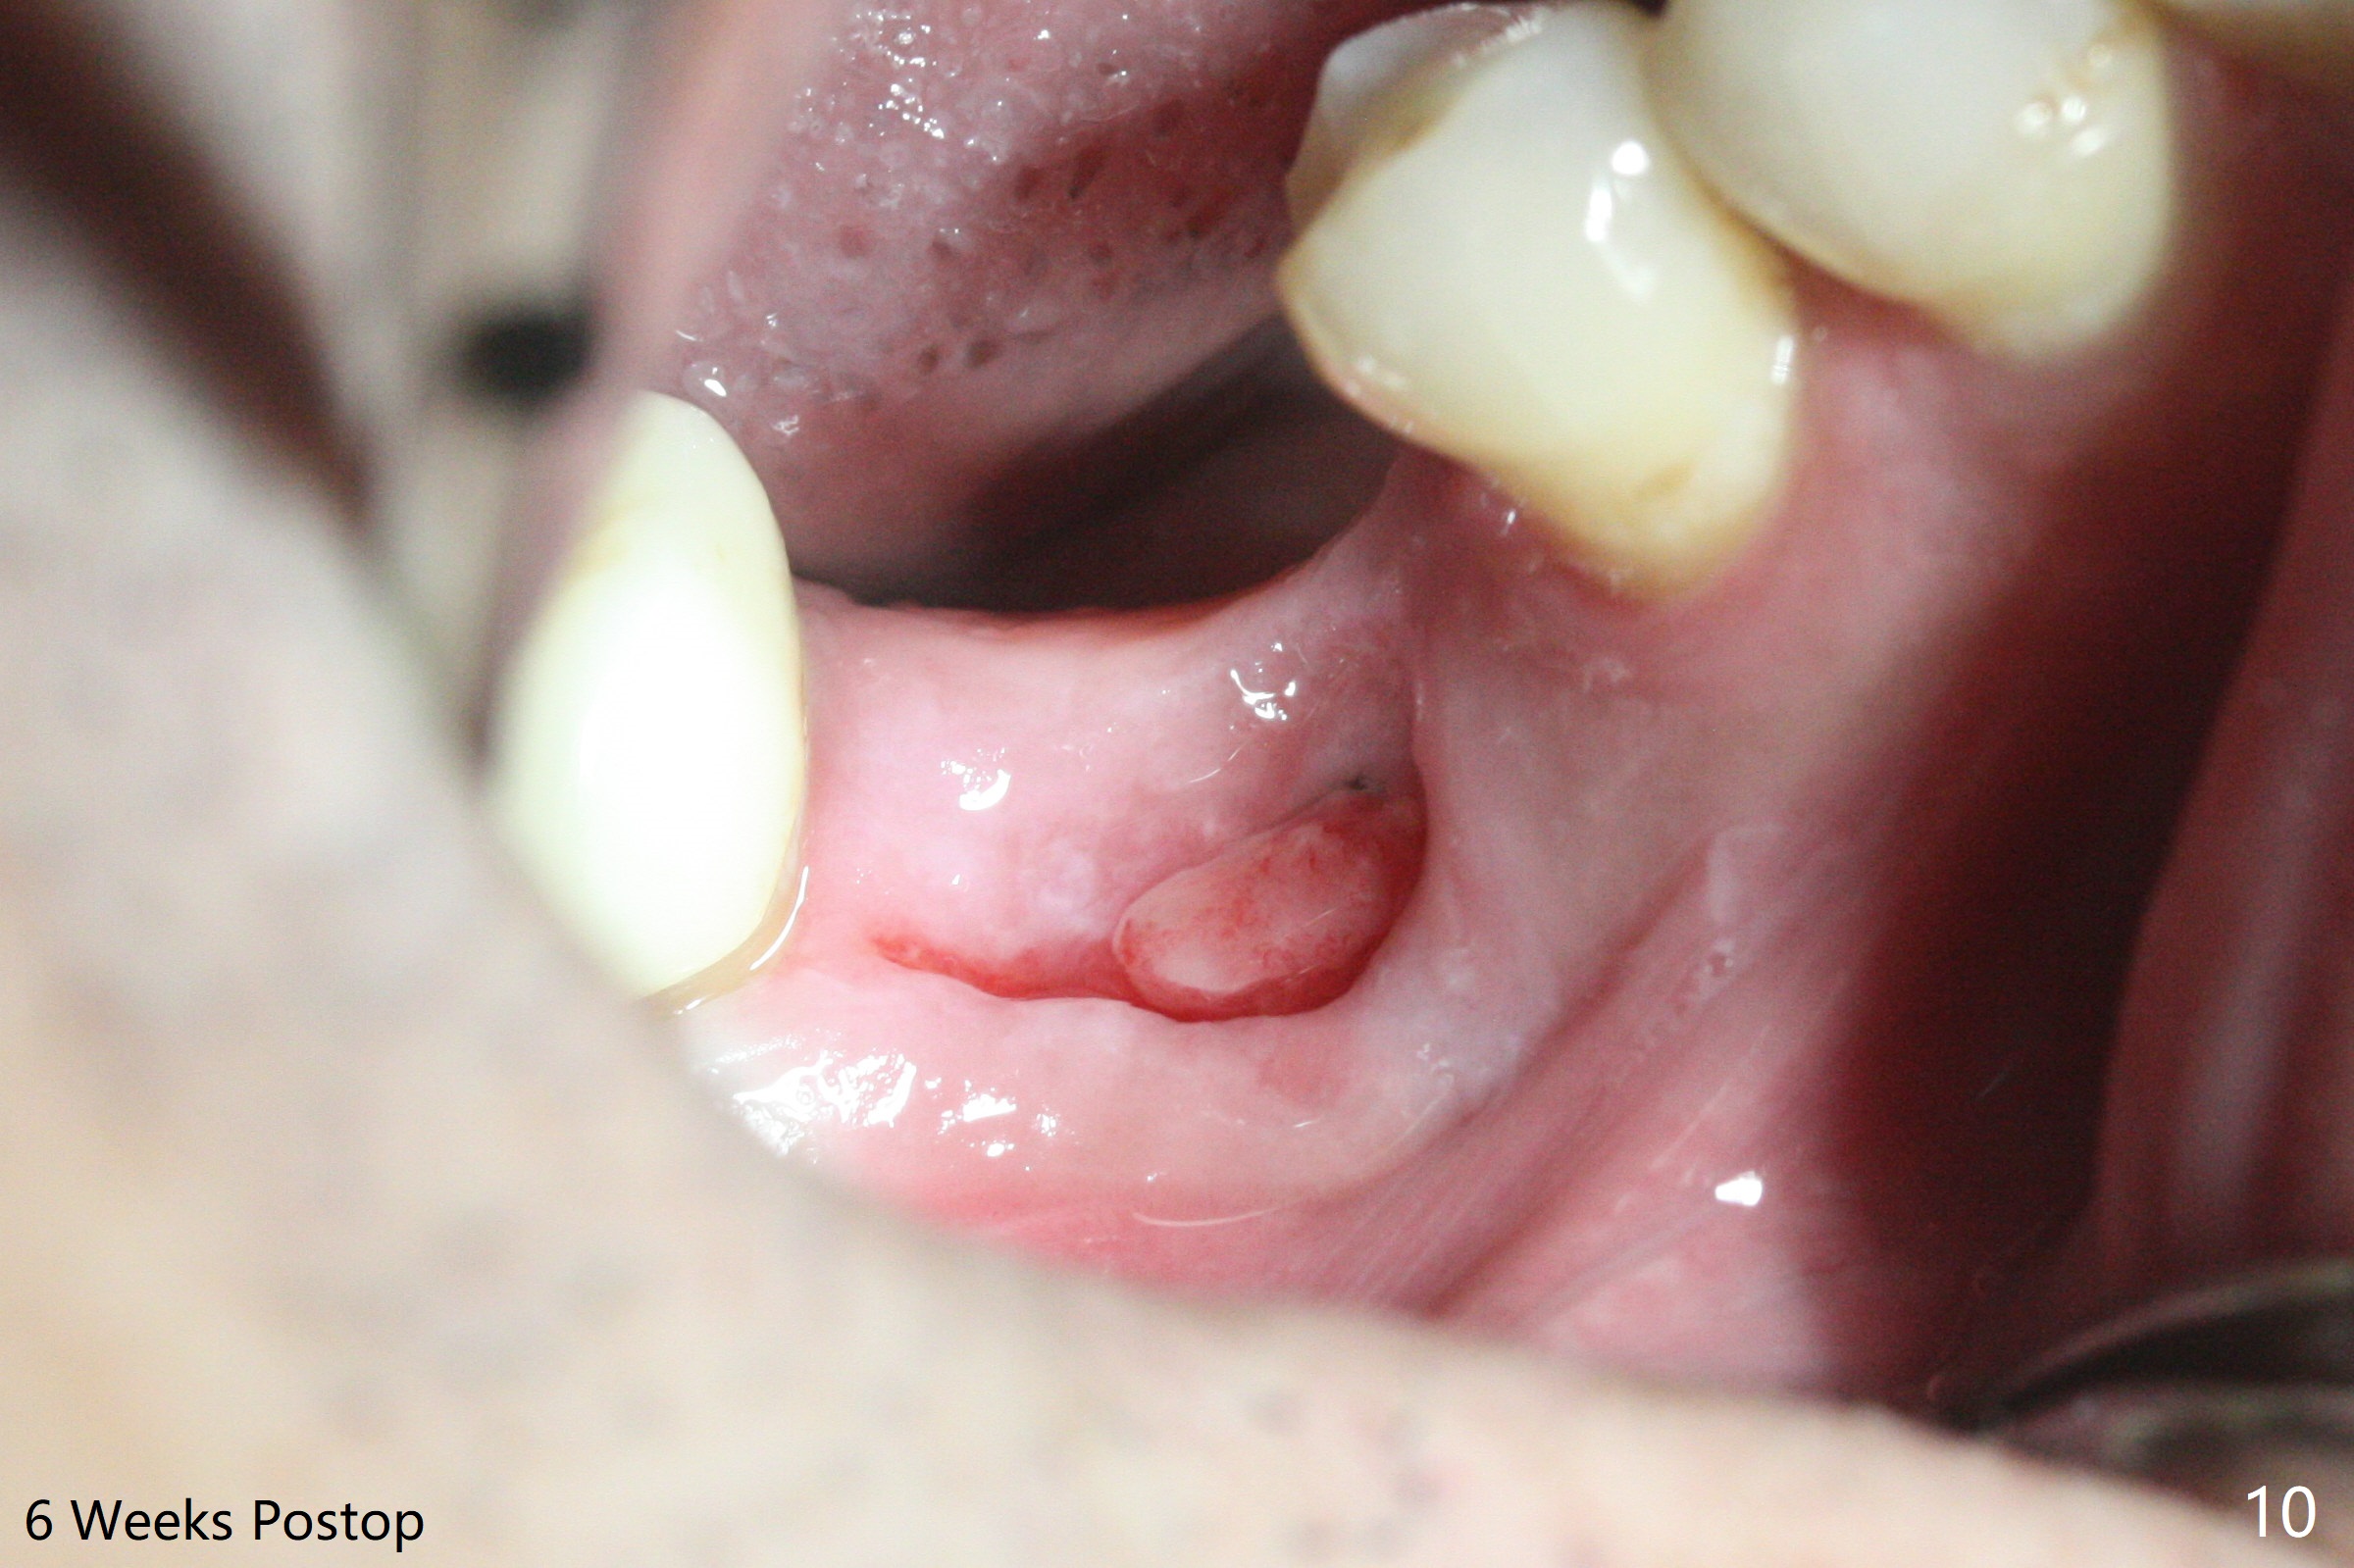

In spite of use of water pik, the coronal threads of the implant at #30 remain exposed 2 months postop (Fig.1). Envelop incision with mesial and distal accessory release ones reveals buccal bony defect (Fig.2). After 2nd spin (1500 RPM for 10 minutes), PRF forms in the red tube (Fig.3 yellow gel-like). Following use of Titanium brush, sticky bone is place (not so bone block-like, Fig.4), followed by a large piece of PRF membrane (from the red tube of Fig.3), Cytoplast (Fig.5,6 white porous) and a small piece of PRF membrane (from the white tube, next to the thin gingiva). The distal (Fig.6 D) and mesial (Fig.7 M) flaps are approximated (arrows without suture) as much as possible as well as lingual. 4-0 Polyglycolic Acid suture is used. Periodontal dressing dislodges 5 days postop. When the patient returns 1 week postop, he is pain free. Although Cytoplast is exposed, the surrounding gingiva seems to be healthy (Fig.8). Later the permanent crown of #31 is temporarily cemented with OHI. It appears that Cytoplast could be used to cover PRF membranes for soft tissue defect, followed by immediate provisional at the stage of immediate implant. The discolored (apparently contaminated) Cytoplast seems to be expelled 6 weeks postop (Fig.9). When the latter is removed, the soft tissue looks normal (Fig.10). Two weeks later, the apparently normal, but thin gingiva forms over the former granulation tissue (Fig.11 *, as compared to Fig.10). There is not enough bone coronal to the implant plateau 2 months post graft (Fig.12). Three months later, bone graft will be re-placed possibly with uncover.